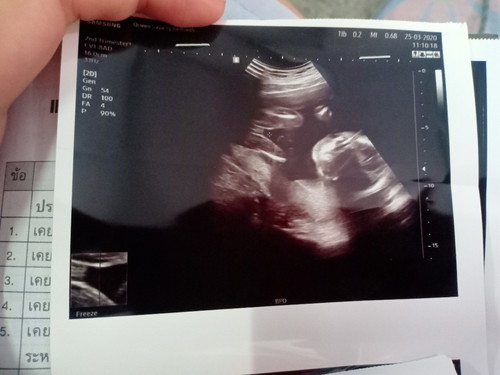

หญิง90%

พึ่งไปซาวมาวันนี้ หมอบอกว่า ได้ผู้หญิง90% แม่ๆบ้านอื่นว่า ชัวร์เรยไหมคะที่จะได้ผญ. แม่บ้านนี้พอหมอบอกลูกสาวดีใจมากเรยค่ะ 20w+5d?

บ้านนี้ไปครั้งแรกบอกผู้หญิง90%ยังกังวลเลยไปรอบ2ตอน6เดือนกว่าหมอก็บอกผู้หญิงค่อยมั่นใจหน่อยเพราะเตรียมแต่เสื้อผ้าสีหวานไว้

บ้านนี้ซาวน์ตอน23w.หมอบอกหญิง100% เห็นเพศชัดมากเลยค่ะ สมใจแม่😁

เหมือนกันค่า 19w1day หมอบอก ผญ ชัดเจนมากมาเป็นกลีบเลย😍😍

ไม่เห็นจู๋น่ะค่ะน่าจะผู้หญิง